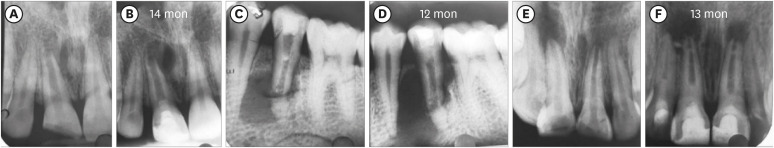

Figure 3

Three cases: platelet-rich plasma group: increased lesion size postoperatively. (A, B) No. 8. (C, D) No. 11. (E, F) No. 12.

Two teeth in the BC group (No. 11 and 12) did not show any sign of BH, and 3 teeth in the PRP group (No. 8, 11, and 12: Figure 3) showed an increased size of the lesion radiographically (Table 1) and were scored 0. In contrast, in the PRF group, all the 11 teeth showed evidence of BH, having a score of excellent (3) in 4, good (2) in 5, and fair (1) in 2 teeth. Among the 3 groups, excellent (3) scores were most often found (n = 6) in the BC group (50%), while 3 teeth exhibited a good (2) score, and 1 tooth had a fair (1) score. In the PRP group, the number of teeth having excellent (3) BH was 3, while a good (2) score was found in 4 teeth, and a fair (1) score in 2 teeth. Considering the number of teeth with good and excellent scores in the 3 groups, it appeared that better BH took place in the teeth of the BC group, followed by the PRF and then the PRP groups, although no significant difference was observed (p = 0.62) (Table 3).

Reduction of PLA was observed in all cases except in the same 3 teeth of the PRP group (No. 8 and 11 [Figure 5], and 12), in which the lesions increased in size (Supplementary Table 1), as was seen in the IOPAR observations. The median percentage reduction in PLA in the PRF group (69.57%; IQR: 23.85%–71.24%) was higher than in the BC group (44.02%; IQR: 25.58%–84.48%) and the PRP group (23.08%; IQR: 31.03%–78.17%). However, this difference was not statistically significant (p = 0.42) (Table 4, Figure 6).